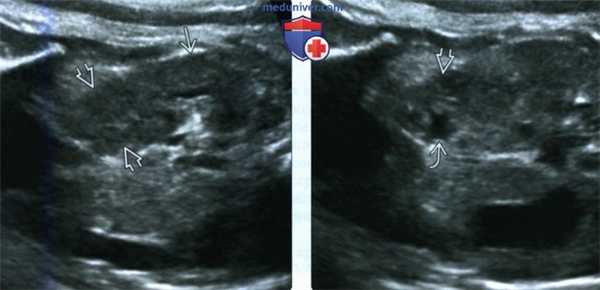

(Слева) УЗИ в продольной плоскости забрюшинного пространства плода во II триместре. Нормально расположенная правая почка с объемным образованием в области нижнего полюса. Эхогенность образования такая же, как у почечной ткани.

(Справа) При смещении плоскости сканирования кпереди видна перекрестная эктопия левой почки со сращением. Лоханка левой почки подтверждает диагноз.